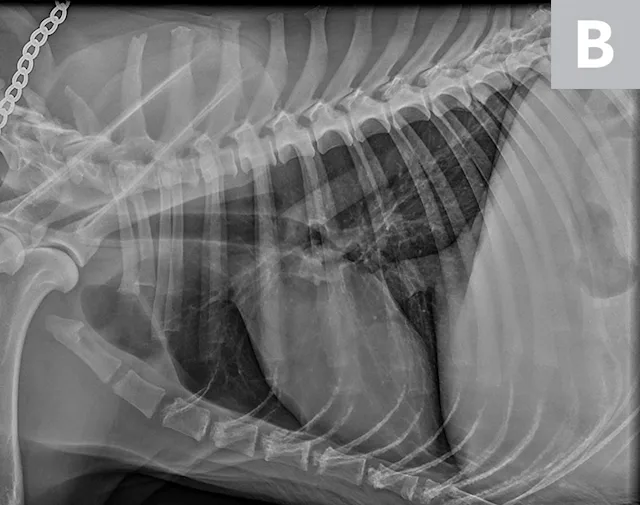

2. Cardiac Silhouette of Dogs on Thoracic Radiographs

The cardiac silhouette can appear larger in small-breed dogs because the heart occupies a large amount of thoracic space; conversely, the cardiac silhouette can appear smaller in large-breed dogs (eg, greyhounds) due to the relatively larger size of the thorax (Figure 3).2

FIGURE 3A

Relative heart size difference on lateral thoracic radiographs of a normal basset hound (A) and a normal greyhound (B).